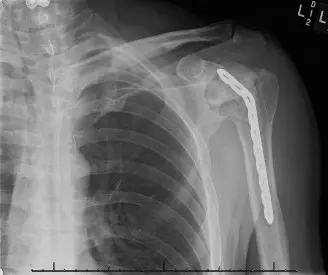

- الأشعة السينية (X-rays) : هي الفحص الأساسي والأكثر أهمية. تظهر الأشعة السينية تضيق مساحة المفصل، وتغيرات في العظام مثل التصلب تحت الغضروف، وتكون النتوءات العظمية (العظم الزائد)، وأي تشوهات في المفصل. في حالات النخر اللاوعائي، يمكن أن تظهر انهيار رأس العظم.

- التصوير بالرنين المغناطيسي (MRI) أو الأشعة المقطعية (CT) : قد تكون ضرورية في الحالات المعقدة، أو عند وجود فقدان شديد للعظام، أو لاستبعاد الأورام، أو لتقييم دقيق للنخر اللاوعائي، أو لتخطيط جراحي أكثر تفصيلاً.